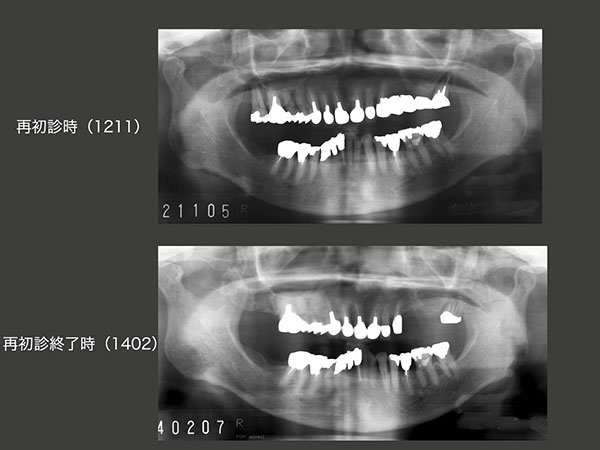

下段は,再初診終了3年3ヵ月(2017年5月)の状態であるが,特に問題ない.

2012年11月再初診時および14年2月再初診終了時のパノラマX線写真の比較.この写真をみると,臼歯部で,歯が咬み合う数は右側の方が多いので,やはり今回も右咬みになり,右側の失活歯の歯根破折に繋がる可能性が高い.患者さんには,右で食事するとき,若い時の80%位の力で咬んでくださいとお願いしているが,なかなか嚙む癖は治らず,また年をとっても咬合力が弱くならないのが現実である.